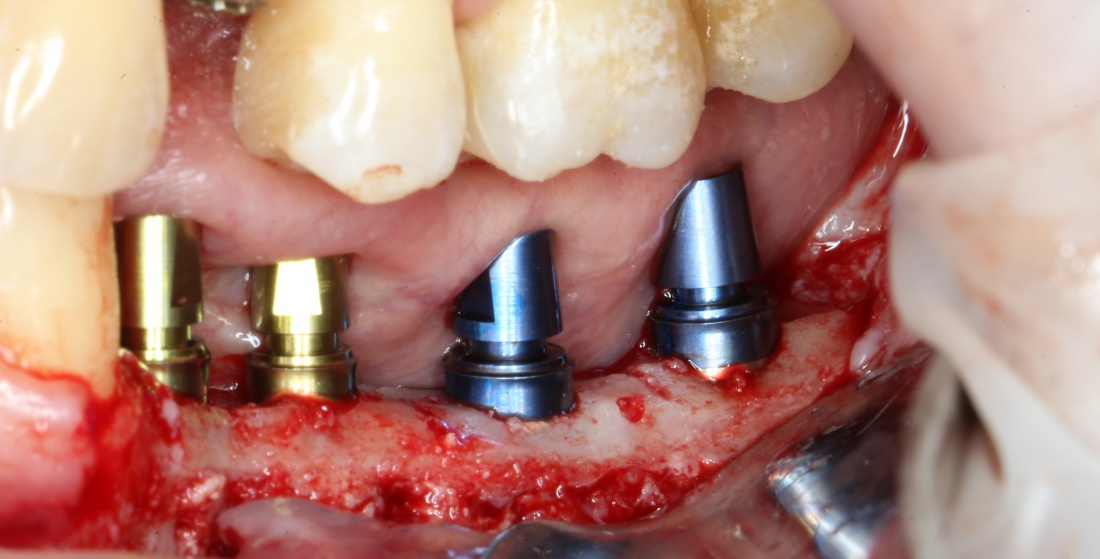

или имплантацией

или направленной костной регенерацией:

Откроем область операции и посмотрим, что там:

Вроде как, всё неплохо. Наверное, можно поставить имплантаты?

ну, или как-то так:

При этом, я хотел бы обратить ваше внимание на один важный момент. То, с чем вы сейчас работаете — не кость, в привычном нам гистолого-физиологическом понимании. Это костная мозоль вперемежку с графтом. Её свойства довольно сильно отличаются от того, что мы привыкли называть костной тканью. Поэтому при установке имплантатов соблюдайте максимальную осторожность и щадящий режим. Никаких диких торков, усилий, больших переходов между размерами фрез допускать нельзя. Будьте аккуратны.